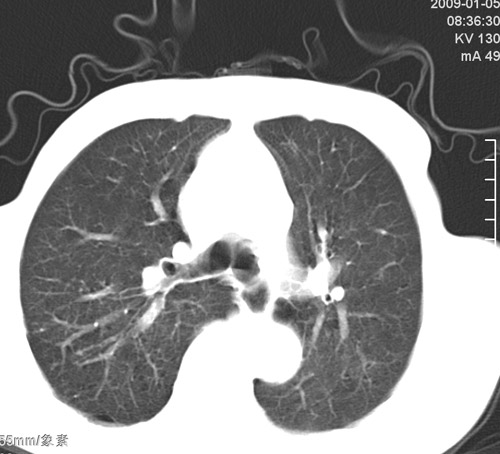

标题: CT17529:男 76 胸背部不适半月 胸透支气管炎 行CT检查 [打印本页]

标题: CT17529:男 76 胸背部不适半月 胸透支气管炎 行CT检查

意见 老年肺 少许炎症 肺大泡 右肺门略大 但支气管通畅  请各位高手指教如何下意见

间质纤维化伴少许炎症!另:肺大泡形成!

支持楼主意见,右肺门略大,可能为肺动脉增粗.

慢支肺气肿,肺动脉高压.